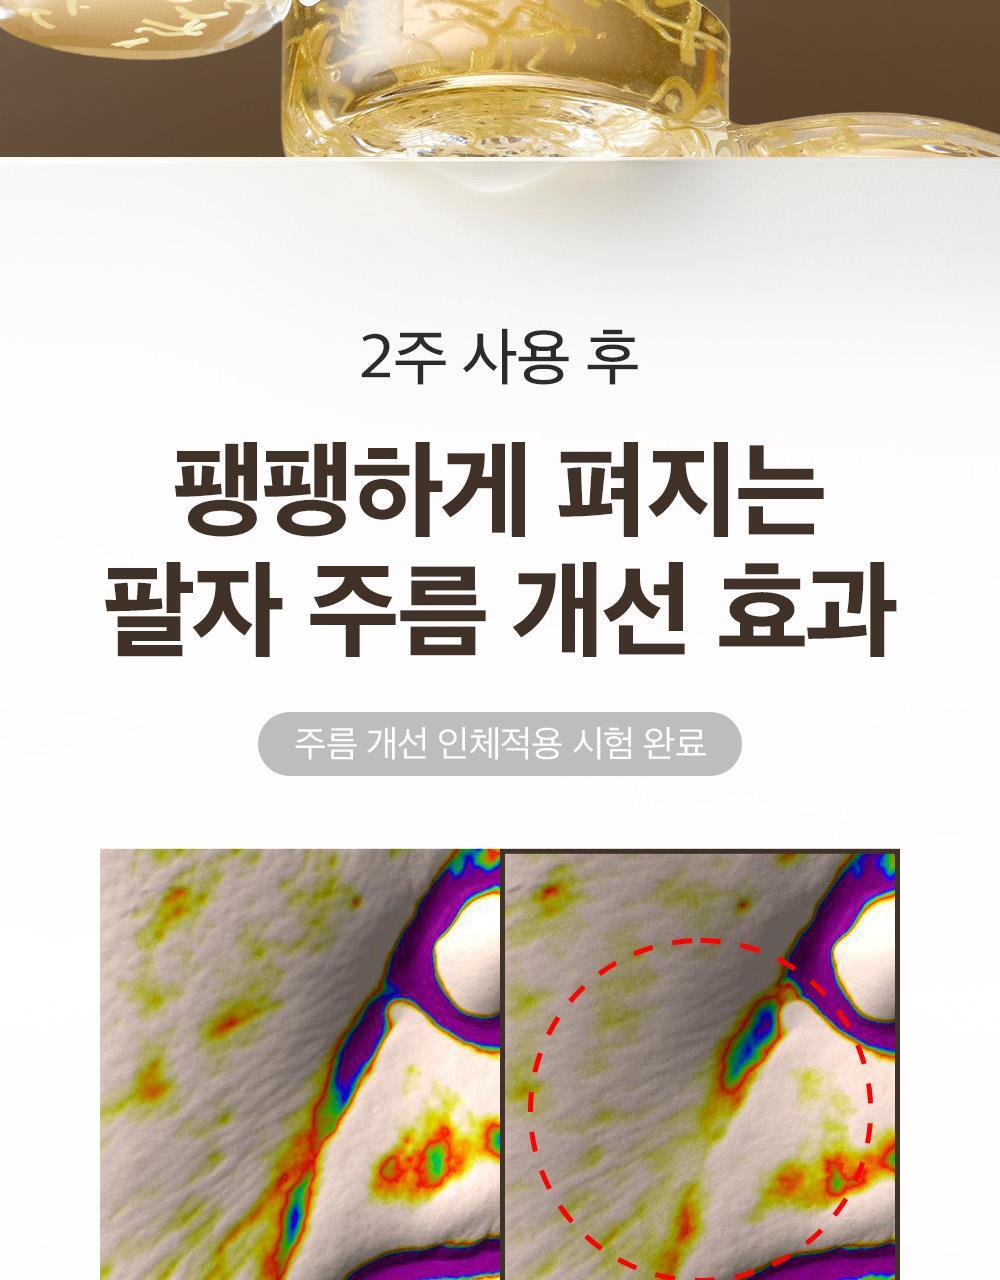

成效數據

額部皺紋起始處提升率:83.57%

臉頰深層脂肪突出處提升率:82.11%

嘴角凹陷處提升率:56.73%

下巴皮膚皺摺處提升率:51.64%

眼周易生皺紋處提升率:47.37%

- 即時效果──「2週持續使用」看得見的改變。